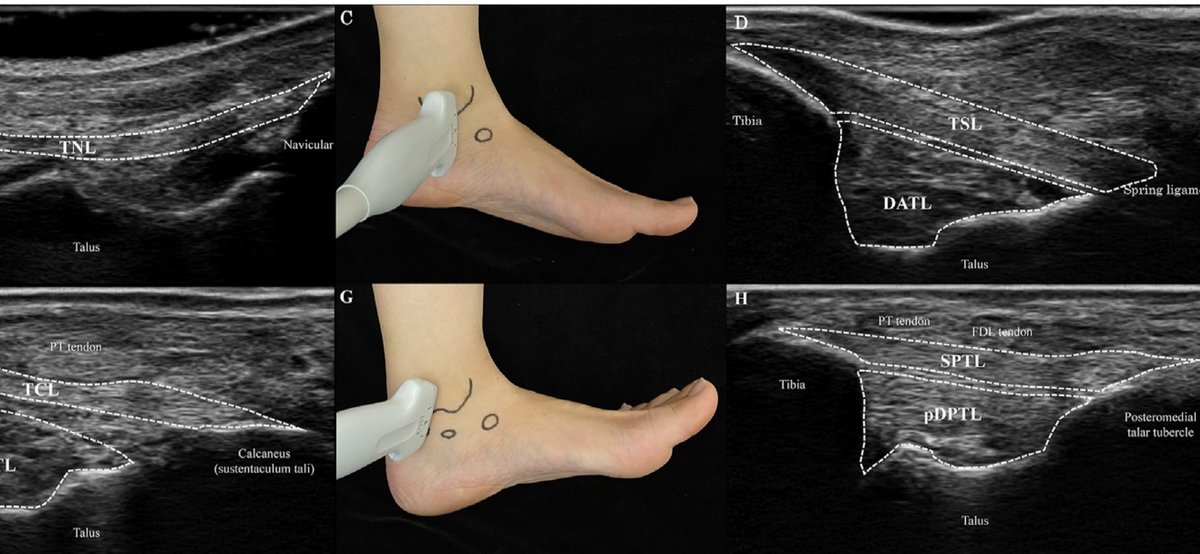

🤔 Repensando el 'Síndrome' del Seno del Tarso: ¿Es realmente un conjunto único de síntomas o varias patologías distintas? Sumérgete en la discusión y descubre por qué la precisión en el diagnóstico es clave. #pieytobillo #ortopedia #traumatología aware.doctor/blog/sindrome-…